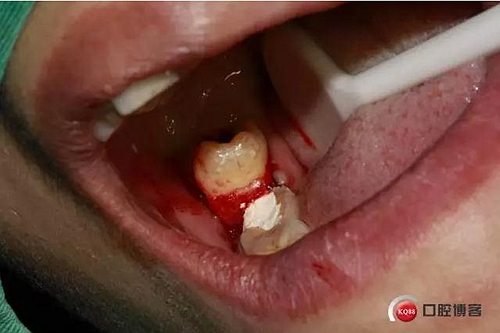

脫位了。

終于下來了。

拔牙創(chuàng)口,清理周邊肉芽,切忌,不能搔刮。